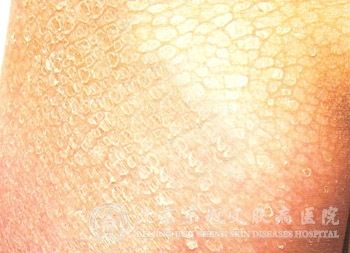

大疱性先天性鱼鳞病样红皮病症状是什么呢?先天性鱼鳞病是鱼鳞病的一种。这种鱼鳞病一般为常染色体隐性遗传性皮肤病。此病的症状为全身或部分表皮过度角化,颗粒层萎缩或消失及皮脂腺萎缩,致使皮肤干燥、粗糙呈鱼鳞状。那么大家知道大疱性先天性鱼鳞病样红皮病症状有哪些吗?

北京京城皮肤医院指出:大疱性先天性鱼鳞病样红皮病分为泛发性与局限性,所以在症状上也存在一定区别。泛发性患者出生便全身有铠甲样厚层鳞甲,生后脱落,出现泛发性潮红及鳞屑,剥除鳞屑呈现湿润面,红斑逐渐消失,可再发生较厚疣状鳞屑;而局限性患者仅在四肢屈侧以及上臂部可有较厚的鱼鳞状角质片。